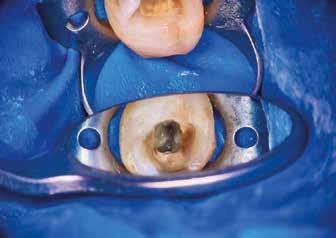

Helyi érzéstelenítést követően kofferdám került felhelyezésre, majd az izolálást folyékony kofferdám felvitelével (RUBBER-DAM liquid, CERKAMED) erősítettük meg (2. ábra). Ezt követően az ideiglenes tömést eltávolítottuk és a pulpakamrát desztillált víz, valamint ultrahangos hegyek segítségével aktivált 5,25%-os NaOCl oldattal megtisztítottuk (3. ábra). Az első mesio-bukkális (MB1), a diszto bukkális (DB) és a palatinális (P) gyökércsatorna átjárható volt, ezért először egy C-PILOT tű (VDW) és egy elektromos apexlokátor (E-PEX, Eighteeth) segítségével ezekben a csatornákban a munkahossz meghatározásra került. Ezután a gyökércsatornákat nagyjából az eredeti munkahossz kétharmadáig

reciprok mozgást végző gépi gyökérkezelő tűkkel feltágítottam (#25/.07 Perfect Shape; Shenzhen Perfect Medical Instruments). Ezt követően az MB2 gyökércsatorna bemeneti nyílását fedő dentint egy gyémánt borítású ultrahangos fej segítségével eltávolítottam (ED3D, Woodpecker). A terület vizsgálatát követően észleltem, hogy az MB1 és MB2 csatornákat egy vékony résszerű nyílás (isthmus) köti össze. Az MB2 csatornának csak a koronális harmadát volt lehetséges kézi eszközök segítségével megmunkálni (4. ábra). Az MB csatornák között lévő rést 2 mm mélységben az előzőleg használt gyémánt borítású ultrahangos fejjel eltávolítottam (5. ábra)

Az átöblítés során a roots magazin egy korábbi számában (2/2022) bemutatott protokollt alkalmaztam (Less-Prep Endo enhanced irrigation protocol). Az átöblítőszer aktiválása SkyPulse lézer (Fotona) segítségével AutoSWEEPS (shock wave enhanced emission photo-acoustic streaming) módban történt. Ennek köszönhetően az MB2 csatorna középső harmada is átjárhatóvá vált a C-PILOT tűk számára. Ezt radio-

lógiai felvételek segítségével is igazoltuk (6–7. ábra). Az MB1 és MB2 csatornák között az átöblítőszerek szabad áramlását észleltük. A gyökércsatornákat crown-down technika szerint a C-PILOT és Perfect Shape gépi gyökérkezelő tűkkel megmunkáltuk, de időhiány miatt a megmunkálás teljes munkahossznál rövidebb mélységben történt. Az ülés végén a fogat kompozitból készült ideiglenes tömés segítségével zártuk és a pácienst egy másik időpontra visszarendeltük.

A következő kezelés elején helyi érzéstelenítést követően kofferdámot helyeztünk fel és az ideiglenes tömést eltávolítottuk. A pulpakamrát desztillált víz, és ED3D ultrahangos hegy segítségével aktivált 5,25%-os NaOCl oldattal megtisztítottuk. A következő cél az MB csatornák közti nyílás ED3D fejjel történő további kitágítása volt. Ezt követően észleltük, hogy az MB2 csatorna bemeneti nyílásának megfelelően strip perforáció alakult ki (8. ábra). Ekkor úgy döntöttem, hogy nem távolítok el további foganyagot, hanem újra elvégzem a Less-Prep Endo átöblítési protokollt. Ennek a hatékony átöblítési protokollnak az elvégzését követően még

potensebb folyadékáramlást lehetett észlelni az MB1 és MB2 csatornák között. Az MB1 és DB csatornákat 25/.07 Perfect Shape gépi tűvel, a P csatornát pedig 45/.04 Endostar E3 Azure gépi tűvel (Poldent) teljes munkahosszon feltágítottam. Végül az összes csatornát átöblítettem 5,25%-os NaOCl és 17%-os EDTA oldattal.

Az MB2 csatornát befecskendezéses technika alkalmazásával egy műgyanta alapú sealerrel töltöttem fel, míg a többi csatornát (MB, DB, P) ugyanezen sealerrel, de meleg guttapercha felhasználásával (continuous wave) töltöttem fel (9. ábra) . A perforációt ezt követően MTA-val (mineral trioxide aggregate) zártam (10. ábra) és kompozittal fedtem (11. ábra) . Több, excentrikus irányból készült periapikális röntgenfelvétel is készült. Ezeken egy további a mesialis gyökér apikális részén végigfutó sealer csíkot és a mesialis gyökér csúcsánál látható sealer puffot sikerült megfigyelni (12–13. ábra)